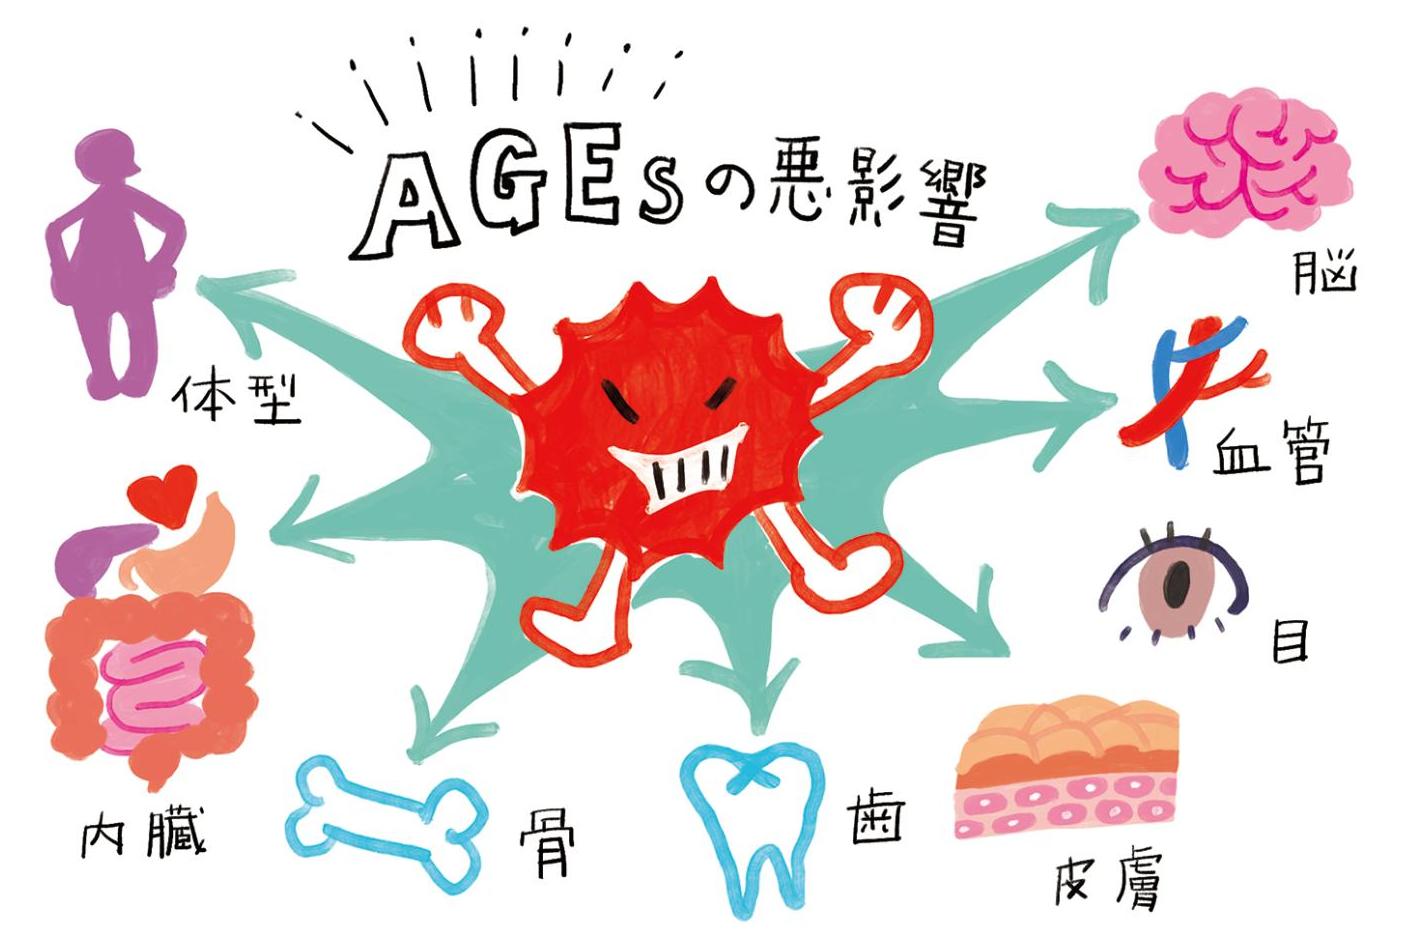

肥満や糖尿病、老け顔…悩みの原因は「糖化」にあり2025.07.01

肥満や糖尿病、老け顔…悩みの原因は「糖化」にあり2025.07.01 -